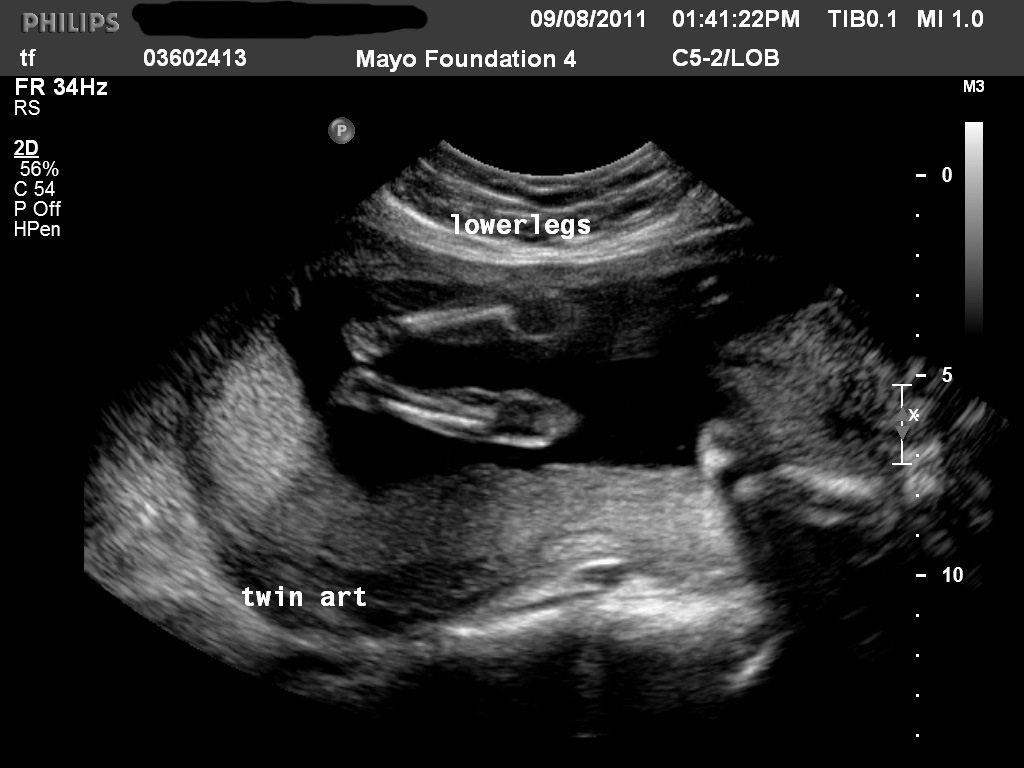

18 Week Twin Ultrasound Twin Pregnancy Twin Anatomy Scan YouTube Can Twins Be Missed At Anatomy Scan Web chances of missing a twin are higher if they share the same amniotic sac. Web today, ultrasound technology allows moms to confirm whether they are having single or multiple pregnancies. Nevertheless, there are a few cases when. Web typically, the doctor will be able to see if there are twins, but sometimes they can be missed at this early. Can Twins Be Missed At Anatomy Scan.